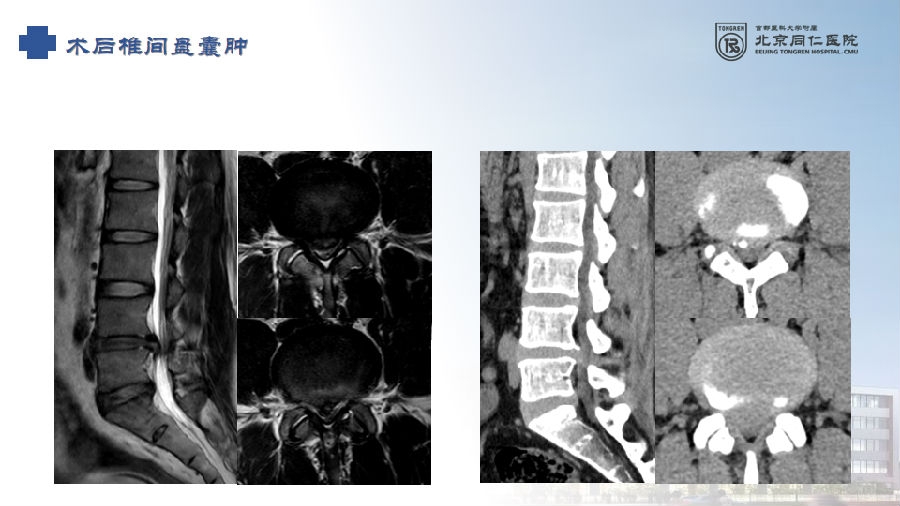

七、术后椎间盘囊肿

病例

男,31岁。

主诉:腰痛伴右下肢疼痛5月,加重2月。

查体:疼痛放射至右侧臀部、大腿外侧、小腿外侧。

思考和建议